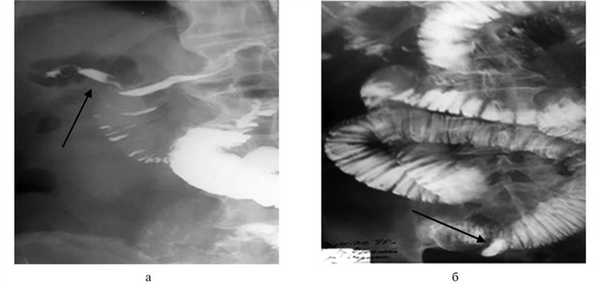

Для оценки пассажа по ЖКТ 11 (64,7%) пациентам выполнено рентгенологическое исследование с водорастворимым контрастным веществом (гастрографин). Пассаж радиофармпрепарата по ЖКТ выполнен 6 (35,3%) пациентам. У 1 (5,9%) пациента установлены показания к операции с диагнозом перитонит на уровне приемного отделения ― больной в экстренном порядке оперирован. Начать проводить консервативное лечение и наблюдение было решено остальным 16 (94,1%) пациентам. Одним из преимуществ использования контрастирования ЖКТ является то, что при наличии фистулы между ЖКТ и желчевыводящими путями возможно контрастирование последних, как итог ― ранняя диагностика билиарной непроходимости. На рис. 2 представлены

Рис. 2. Рентгенограммы пассажа водорастворимого контраста по тонкой кишке. а ― контрастирование внепеченочных желчных протоков; б ― конкремент в тонкой кишке. рентгенограммы, на которых имеются патогномоничные признаки обтурационной билиарной кишечной непроходимости: контрастирование внепеченочных желчных протоков и контрастирование конкремента.